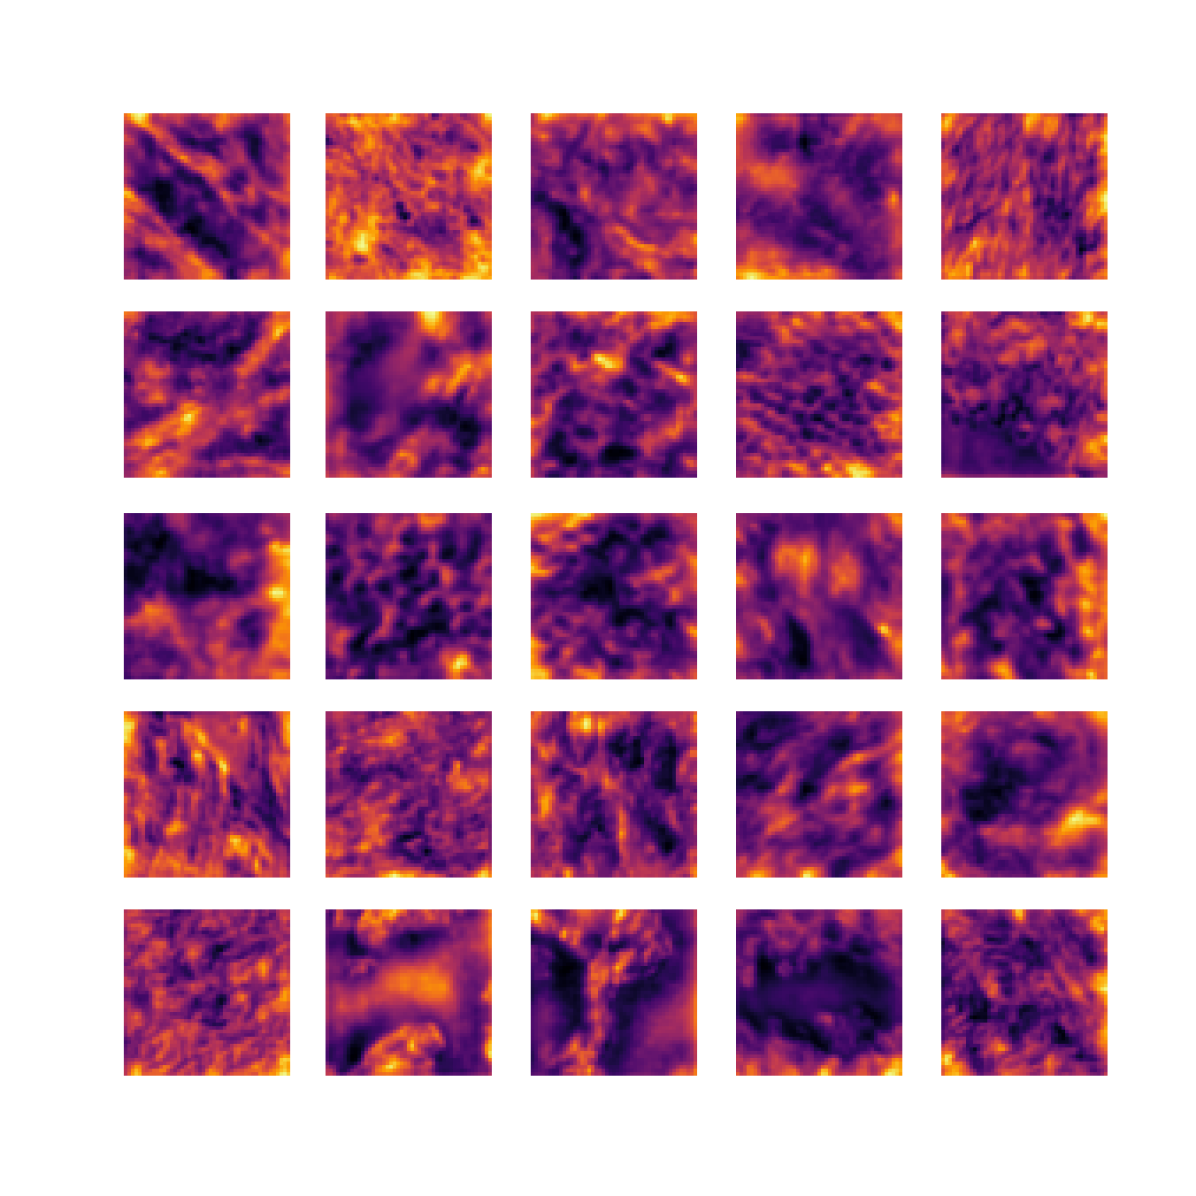

We also analyse the activation maps for each model using GradCAM as described in section S3. This offers more insight into the areas of the image which are contributing most heavily to the models’ representations. In Figure 4(b) we present some representative examples, however, a larger selection which was chosen at random is presented in Figures S10 to S25. The larger selection makes it easier to see the emergent patterns, including that privileged Siamese models tend to mainly identify features which are strongly present in both inputs, while unprivileged Siamese models tend to learn more diffuse features that are not specific to one cell phenotype or image region. TriDeNT ♆ incorporates both sets of features, learning both features specific to the privileged data and more the general features associated with unprivileged Siamese networks.

We can see in Figure 4(b) panel A that for ERG, the privileged Siamese model focuses almost exclusively on any nuclei which could be endothelial cells. As there are very few endothelial cells in the dataset, it could be an effective strategy to identify anything that could potentially be an endothelial cell to minimise the difference between the representations of the H&E model and the IF mask model. In the corresponding unprivileged Siamese image, we see that the model identifies some of these nuclei, albeit less strongly, but also focuses heavily on the other tissue and even the background, while strongly fixating on two spots of debris in the center of the image. This model has less ‘incentive’ to learn the weak features related to endothelial cells as these occur rarely and are not easy to detect, while more generic strong features such as the presence of connective tissue and the prevalence of background are more common and predictable from augmented images. We see that TriDeNT ♆ combines these two feature sets, strongly identifying nuclei while also identifying the connective tissue.

In panel C we see a similar pattern, with the privileged Siamese model fixating solely on the nuclei, while the TriDeNT ♆ model takes a more balanced approach. The unprivileged Siamese model appears to focus on a single cluster of nuclei while neglecting others, and similarly identifies an area of fibroblasts with its distinctive pattern but does not others.

In contrast to panels A and C which represent models with poor privileged Siamese results, panels B and D represent models whose privileged Siamese results were comparable to both TriDeNT ♆ and even the supervised baseline. It is therefore interesting to note that there are far more similarities between the privileged Siamese and TriDeNT ♆ models in both cases. Particularly in panel B, TriDeNT ♆ and the privileged Siamese model return virtually identical heatmaps, with both strongly identifying epithelial nuclei and neglecting the same areas of connective tissue. The unprivileged model in this case appears to focus solely on the centre of the image, giving a significantly different heatmap to the other panels.

Panel D again shows the previous pattern, with the privileged Siamese model identifying the features strongly present in the privileged data – fibroblasts – while neglecting the nuclei present. TriDeNT ♆ also strongly identifies the connective tissue, but, unlike the privileged Siamese model, does not completely neglect the nuclei. The unprivileged Siamese model primarily identifies background, and does not appear to identify the nuclei in this example.